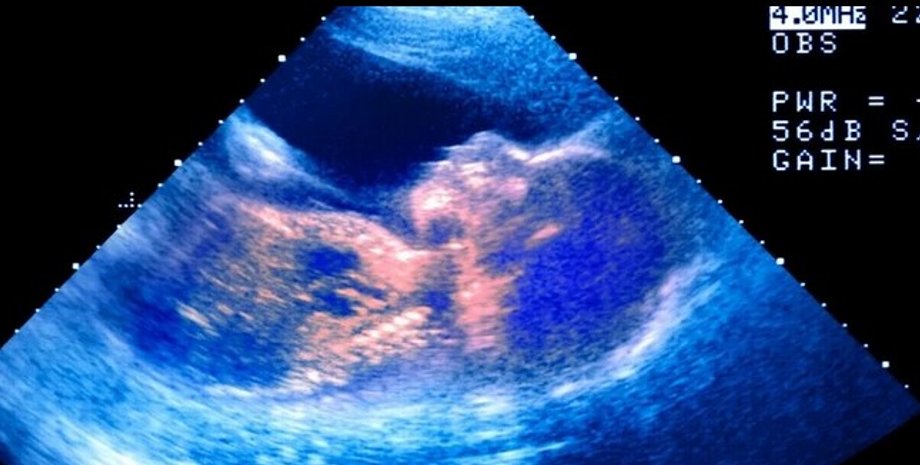

Плод, ребенок, ультразвук, утроба

Фото: ScienceAlert

Начиная со второго триместра беременности, мама может почувствовать, как ребенок пинается и переворачивается, но может ли он плакать? С помощью ультразвука ученым удалось увидеть, как у плода, возрастом 33 недели, на лице была мимика, которая была похожа на плач. После этого ученые провели вибрационную и шумовую стимуляцию плода и заметили интересное поведение, сообщает ScienceAlert.

Во время стимуляции младенец широко открыл рот, сделал несколько выдохов и запрокинул голову, все закончилось дрожью подбородка. Подобное поведение было замечено у 10 младенцев. Был ли это плач? Все зависит от того, что вы подразумеваете под плачем, говорят ученые.